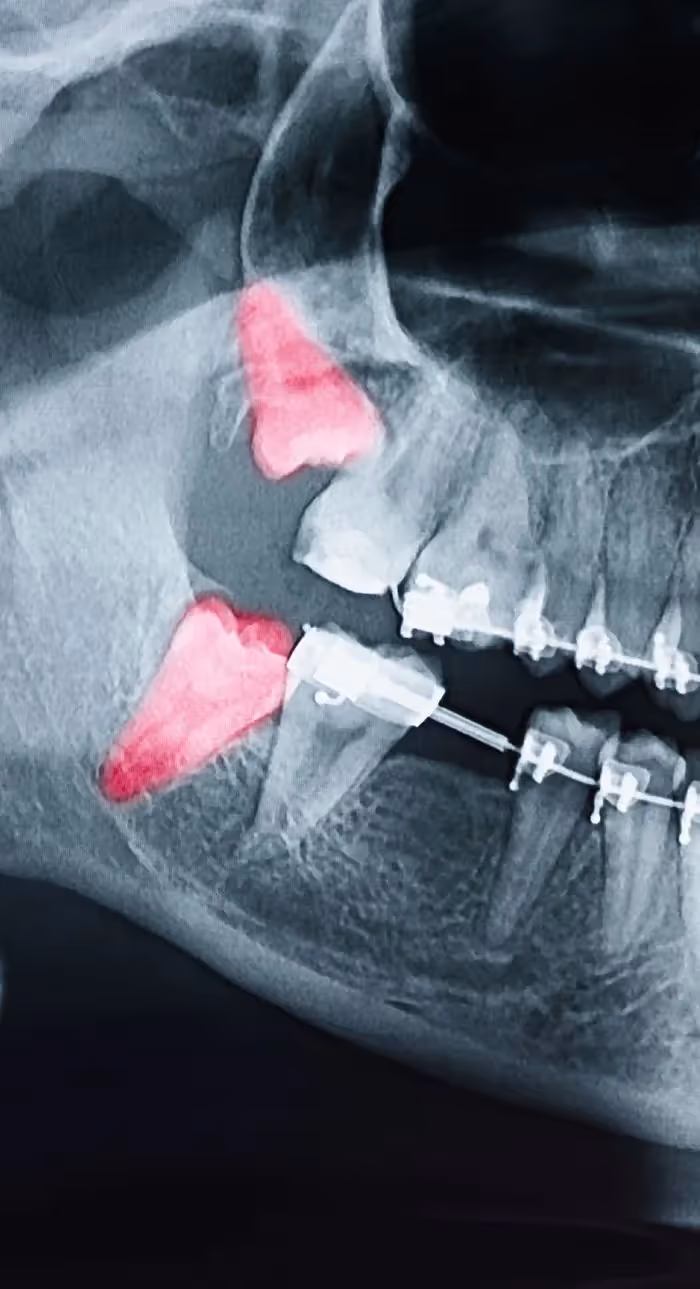

The most common reason for tooth extractions is improper wisdom teeth growth. If your dentist determines that your wisdom teeth are impacted or not erupting correctly, extraction may be recommended to protect the health of your other teeth. Not everyone requires wisdom teeth removal, so it’s important to consult your dentist to determine if yours pose a problem.

Problematic teeth negatively impact your overall oral health. Our team prioritizes preserving your natural teeth, but sometimes an extraction is the best way to save your smile. There are various reasons for needing a tooth extracted. Wisdom teeth often cause discomfort that can be relieved through extraction, and some advanced restorative procedures, like dental implants, require the removal of unhealthy teeth. Using gentle techniques and local anesthesia, tooth extractions can be quick and painless.

Tooth extractions may be needed for patients dealing with extremely severe cavities, significant damage from trauma, or a tooth infection that can’t be resolved with root canal therapy. While most teeth can be saved through crowns or root canals, sometimes extraction is the only viable option.